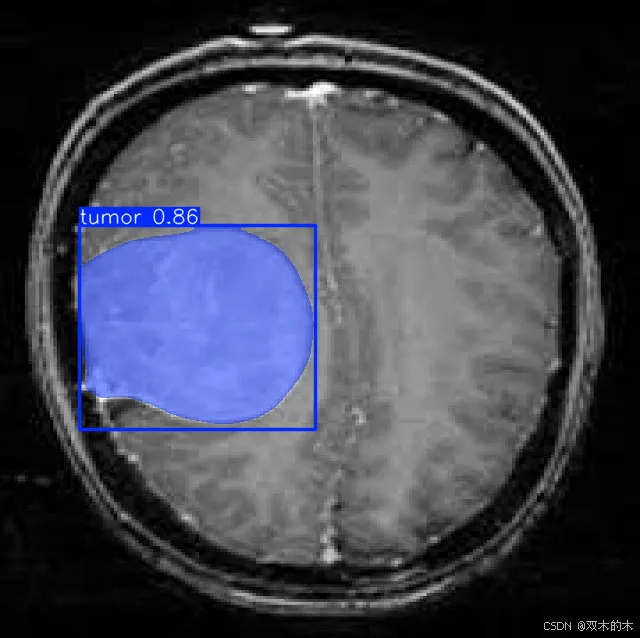

数据收集:收集表示要检测的类的图像。在此示例中,我们将使用 BRAIN-TUMOR 数据集,其中包含来自 roboflow 的 834 张图像。

链接 :https://universe.roboflow.com/iotseecs/brain-tumor-yzzav

YOLOv11 作为强大的实例分割工具脱颖而出,结合了尖端的准确性和效率。按照本文中概述的步骤,您可以在自定义数据集上有效地训练 YOLOv11 模型,并将其功能用于各种应用程序。